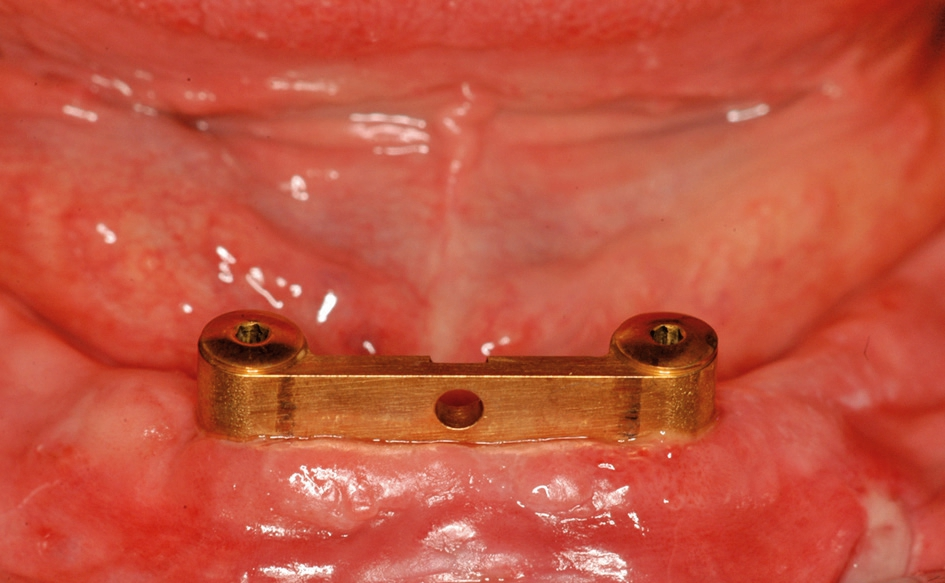

Abb. 13: Direkt nach der Implantation wird der Steg definitiv montiert und die Schrauben mit 30 N/cm festgezogen.